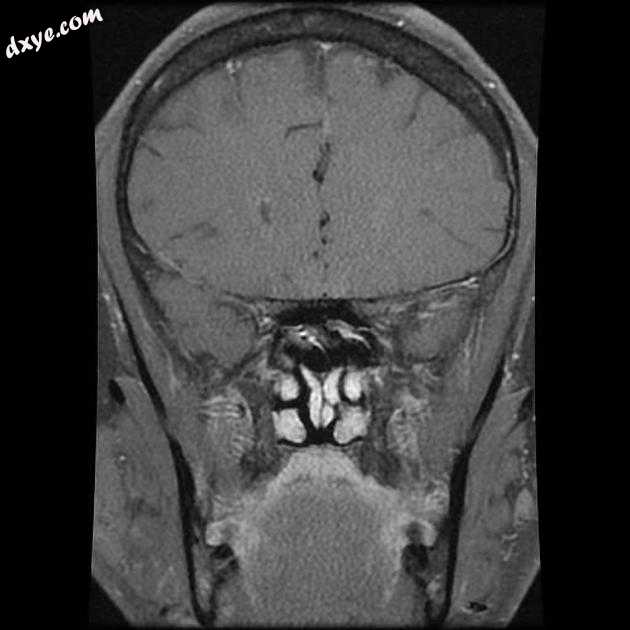

Axial T1

MRI 序列显示右侧颈内动脉的部分血栓囊状动脉瘤位于 C6/7 节段的交界处,大小为 11 x 7 毫米,颈部为 2.5 毫米,压迫动眼神经 (III) 的相邻节段,在 T1 上清晰可见和 FIESTA 序列。

位于 C6/7 交界处的右侧颈内动脉部分血栓囊状动脉瘤的 MRI 特征,压迫同侧动眼神经 (III)。